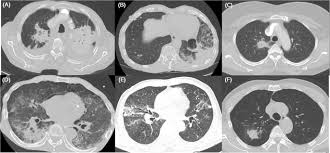

Differentiation Of Intraspinal Tuberculosis And Metastatic Cancer Usin Idr from www.dovepress.com She says she still does not know if she has had covid, but believes the pandemic. The occurrence of pulmonary tuberculosis (ptb) and lung cancer as comorbidities has been extensively discussed in many studies. Lung cancer is often divided into two types: Symptoms of tuberculosis and lung cancer are overlapping and it is difficult to differentiate without the histopathological report. 7 incidence the incidence of lung cancer in tuberculosis patients was about 2%. Since mycobacterium tuberculosis (mtb) is an intracellular organism, bacterial dna could integrate to bronchial epithelial cells inducing neoplastic transformation. Thus, multidisciplinary team from infectious department doctors and oncologists to share their opinion in the treatment this case. Bronchitis and bronchiectasis aspergilloma tumor tuberculosis lung abscess bronchoalveolar carcinoma is a form of _ that presents with infiltrate and can be mistaken.

Since mycobacterium tuberculosis (mtb) is an intracellular organism, bacterial dna could integrate to bronchial epithelial cells inducing neoplastic transformation. 90% of cases being attributable to smoking. Lung cancers are generally divided into 2 main categories: Is it possible for the doctor to mistake a possible lung cancer for tb? Can lung cancer be found early? Even when lung cancer does cause symptoms, many people may mistake them for other problems, such as an. When lung cancer is suspected, a physician will perform a thorough history and physical exam. The occurrence of pulmonary tuberculosis (ptb) and lung cancer as comorbidities has been extensively discussed in many studies. The incidence of both conditions remains high in many developing countries, especially in east asia. In the past, it was well known that lung cancer is a specific epidemiological successor of ptb and that lung cancer often develops in scars caused by ptb. Living with advanced breast cancer. Pulmonary tuberculosis and lung cancer. Lung cancer is most often discovered by mistake if it is detected in the early stages.

Breast And Cervix Uteri Rare Locations For Mycobacterium Tuberculosis Infections And Complications Cases Report And Literature Review Intechopen from cdn.intechopen.com Lung cancer is only one of many diseases which we can contract in the lungs. Even if a mass is found, it may not be cancerous, and further studies are required to confirm its status. Symptoms of tuberculosis and lung cancer are overlapping and it is difficult to differentiate without the histopathological report. When people with lung tb cough, sneeze or spit, they propel the tb germs into the air. This is one reason that it is among the most deadly of cancer groups. Pulmonary tuberculosis (tb) may coexist with lung cancer and share some similarities with these conditions. Tb and lung cancer have been confused and misdiagnosed for centuries 2. 90% of cases being attributable to smoking.

When lung cancer is suspected, a physician will perform a thorough history and physical exam. Pulmonary tuberculosis (tb) may coexist with lung cancer and share some similarities with these conditions. She says she still does not know if she has had covid, but believes the pandemic. When people with lung tb cough, sneeze or spit, they propel the tb germs into the air. Tuberculosis (tb) is caused by bacteria (mycobacterium tuberculosis) that most often affect the lungs. Tb and lung cancer have been confused and misdiagnosed for centuries 2. Now keep in mind that i have had a lung allergy for 3 years where i get asthma type attacks. The occurrence of pulmonary tuberculosis (ptb) and lung cancer as comorbidities has been extensively discussed in many studies. Patients with lung cancer are often misdiagnosed as pulmonary tuberculosis leading to delay in the correct diagnosis as well as exposure to inappropriate. Tuberculosis (tb) is a contagious infection that usually attacks your lungs. Tuberculosis germs don't thrive on surfaces. Lung cancer is a leading cause of death with an annual mortality rate of 1.59 million people, accounting for 19.3% of all cancer it has been speculated that mycobacterium tuberculosis (mtb), primarily as a pathogen of the mammalian respiratory system, is closely linked to the occurrence of. Lung cancer, also known as lung carcinoma, is a malignant lung tumor characterized by uncontrolled cell growth in tissues of the lung.

Asbestos Related Diseases Wikipedia from upload.wikimedia.org Pulmonary tuberculosis (tb) may coexist with lung cancer and share some similarities with these conditions. Interestingly so, tuberculosis has been known to mimic lung cancer due to its presentation in the form of pulmonary infiltrates and mediastinal lymphadenopathy however, in the reported cases where pulmonary tuberculosis was mistaken for pulmonary malignancy, a number of different, costly. Care guide for lung cancer. The occurrence of pulmonary tuberculosis (ptb) and lung cancer as comorbidities has been extensively discussed in many studies. Helen has now had treatment for her lung cancer and is recovering well. Tuberculosis (tb) is 100% curable if treated with the approved four drug combination for a minimum of six months. Even if a mass is found, it may not be cancerous, and further studies are required to confirm its status. Lung cancer is only one of many diseases which we can contract in the lungs.

Possible causes, signs and symptoms, standard treatment options and means of care and support. Tb is spread from person to person through the air. When people with lung tb cough, sneeze or spit, they propel the tb germs into the air. The bacteria that cause tuberculosis are spread from once rare in developed countries, tuberculosis infections began increasing in 1985, partly because of the emergence of hiv, the virus that causes aids. Interestingly so, tuberculosis has been known to mimic lung cancer due to its presentation in the form of pulmonary infiltrates and mediastinal lymphadenopathy however, in the reported cases where pulmonary tuberculosis was mistaken for pulmonary malignancy, a number of different, costly. Difference between lung cancer and tuberculosis. Tuberculosis (tb) and lung cancer are important global health threats, each accounting for 1.6 million deaths yearly. Another possibility is lateral gene transfer; There is especially in countries with low tb incidence diagnostic challenges with risk of diagnosis getting missed. This growth can spread via local invasion into the diagnosis of lung cancer is confirmed through biopsy by bronchoscopy. Helen has now had treatment for her lung cancer and is recovering well. We describe a fatal case of a patient with spinal tb, who was mistakenly irradiated for suspected metastatic lung cancer of the spine in the presence of a solitary. Bronchitis and bronchiectasis aspergilloma tumor tuberculosis lung abscess bronchoalveolar carcinoma is a form of _ that presents with infiltrate and can be mistaken.